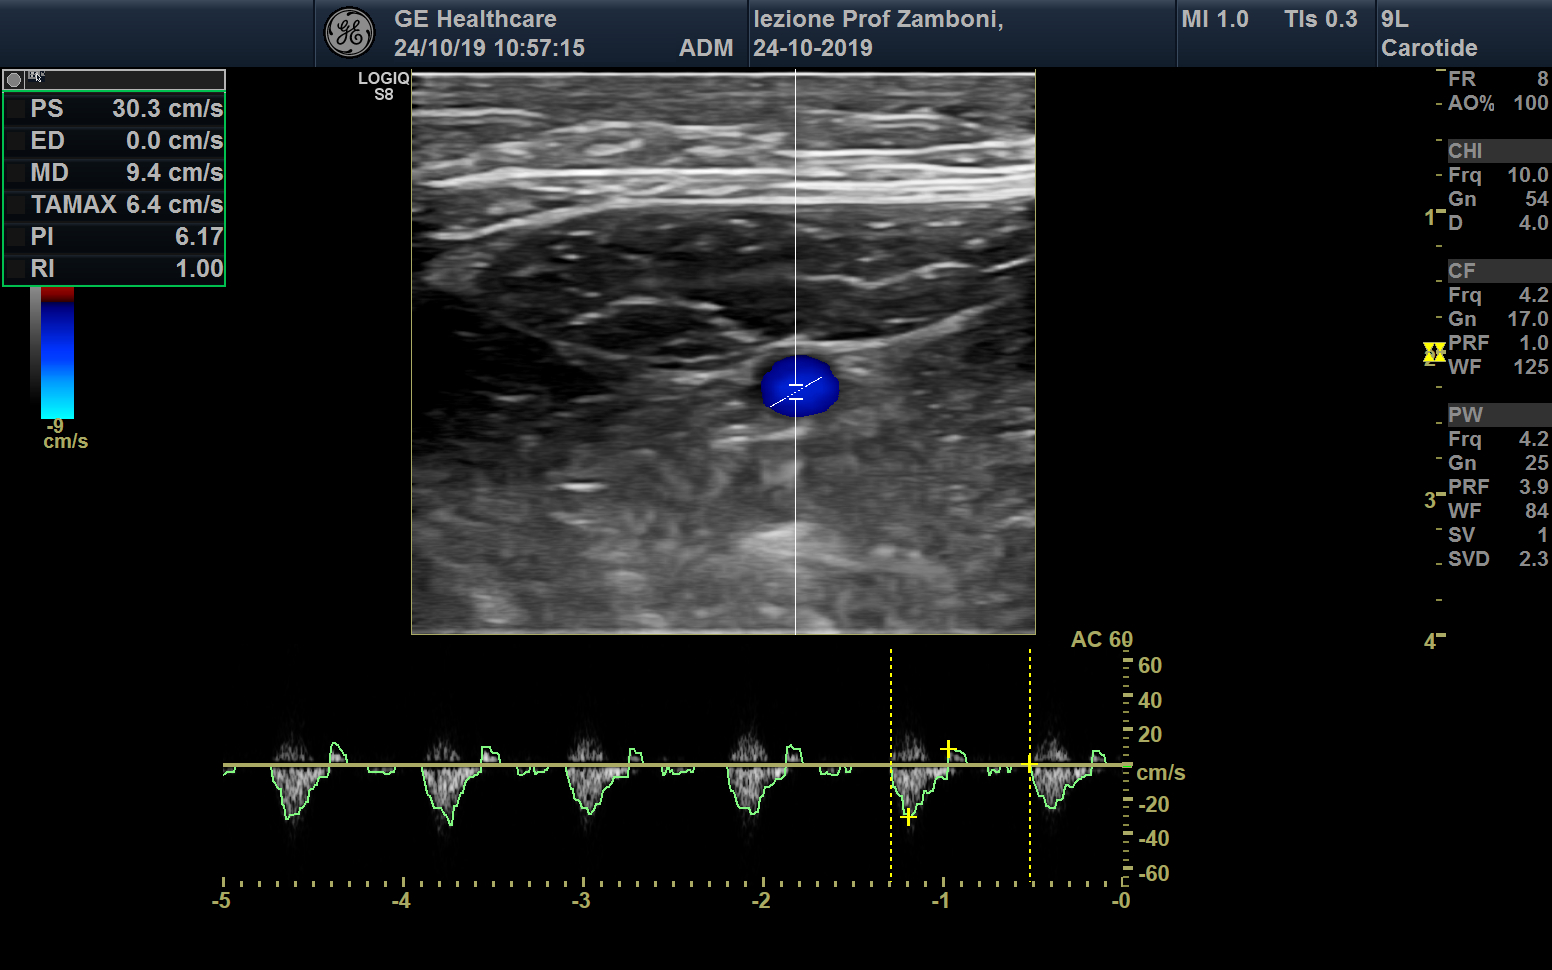

PW A. Femorale

JPEG image icon PW A. Femorale.jpg — JPEG image, 570 kB (584513 bytes)